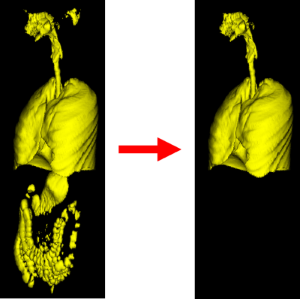

Далее выделим дыхательные органы как максимальный по объему объект. Дыхательные органы — это отдельный объект. Связи между легкими и воздухом внутри желудочно-кишечного тракта нет.

Для захвата сосудов внутри лёгких применим морфологическое закрытие, то есть дилатацию с последующей эрозией с тем же радиусом. Рентгеновская плотность сосудов составляет около -100..100 HU.

Крупные кровеносные пути не закрылись. Но в этом и нет необходимости. Цель данной операции была в уничтожении множества мелких отверстий внутри легких для упрощения дальнейшей сегментации легких.